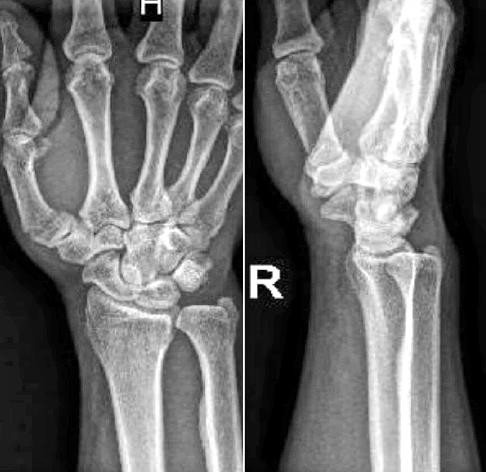

A detailed history taken before the patients were subjected for the surgery. The patients were also subjected for the detailed physical examination. X-ray with AP, oblique/lateral views were done, Routine investigations as per the institution protocol were sent. All the patients were subjected for Pre-anesthetic check-up and clearance. In case of open fractures, debridement of the wound and thorough irrigation was done with normal saline.

Closed/open reduction was achieved by traction and manipulation. To maintain reduction, percutaneous Kirschner-wire or Joshi’s external stabilization system were used. Image intensifier (C-arm) was used as a guide for the steps mentioned above. Post-operatively, x-rays were taken to evaluate the fixation. Patients were taught active mobilization of the unaffected fingers, elbow and shoulder from immediate post-op period. Pin tract dressings were done regularly. Patients were called for periodic evaluation at 2 weeks, 4 weeks, 6 weeks and 8 weeks on OPD basis to assess:

About 63.3% of patients and 13.3% of patients of group A and group B respectively had Type I fractures. 30% of group A and 50% of the patients of group B had Type II fractures. 6.7% of group A and 36.7% patients of group B had Type IIIA fractures. This difference in type of the fractures was statistically significant between the two groups.